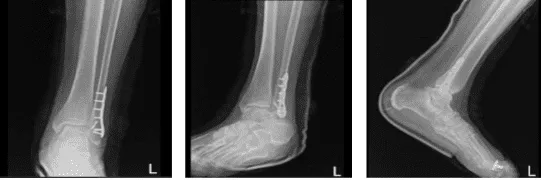

Un paciente masculino de 78 años acude a la consulta con radiografías presentadas y quejas por el dolor en el pie izquierdo y tobillo tras resbalar en hielo hace tres días. El paciente afirma que el dolor presenta síntomas asociados como hinchazón, inestabilidad y sensibilidad al tacto.

Se revisaron y discutieron las radiografías y se le diagnosticó fractura cerrada de la maléola lateral – Fractura desplazada de la maléola lateral de la fíbula izquierda, encuentro inicial de fractura cerrada.

Dos semanas después de la cirugía, el paciente fue atendido en la consulta para sus visitas postoperatorias, el médico revisó y discutió las radiografías. La placa quirúrgica y los tornillos fijan el peroné distal izquierdo con una alineación casi anatómica. El hardware parece intacto y la tibia distal también está intacta.

Los aspectos visualizados del astrágalo izquierdo, el calcáneo y los huesos tarsianos muestran márgenes corticales intactos sin evidencia de fractura aguda. No hay cambios degenerativos significativos, la mortaja del tobillo está bien mantenida.

Hay una leve hinchazón de tejidos blandos. Se observa una férula suprayacente y no hay espolones plantares calcáneos. Lo que significa que la fractura del peroné distal izquierdo tratada quirúrgicamente con alineación casi anatómica.

Radiografía del tobillo izquierdo completada